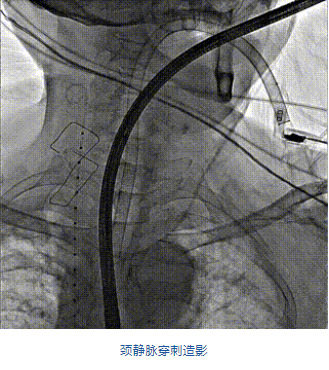

2022年5月27日,四川大學華西醫院心臟內科陳茂、馮沅教授帶領的瓣膜病介入治療多學科團隊,在國內首次采用純介入方式通過穿刺右側頸靜脈成功完成經導管三尖瓣置換。植入的人工瓣膜是具有中國自主知識產權的LuX-Valve Plus系統。術中上海長海醫院陸方林教授和喬帆副教授給予了在線支持。

團隊前期經過多次討論,制定了周密的手術策略和預案。由于患者已是近九旬的超高齡老人,傳統外科開胸手術風險極高,純介入經血管三尖瓣替換能夠明顯減少創傷。術中陳茂及馮沅教授結合體表定位在造影指示下精準穿刺右側頸靜脈并預置兩把血管縫合器。成功建立經皮血管入路后在食道超聲和DSA的引導下順利完成人工瓣膜植入,術后超聲和造影顯示人工三尖瓣同軸性良好,瓣架固定牢靠,無反流和瓣周漏,平均跨瓣壓差降為1mmHg。術畢收緊預置的血管縫合器縫線完成止血,縫合效果滿意,在手術室即刻拔除氣管插管。